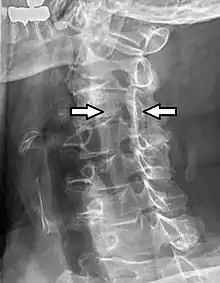

Cervical spinal nerve 4 Projectional radiograph of a man presenting with pain by the nape and left shoulder, showing a stenosis in the intervertebral foramen of cervical spinal nerve 4, corresponding with the affected dermatome.

Projectional radiograph of a man presenting with pain by the nape and left shoulder, showing a stenosis in the intervertebral foramen of cervical spinal nerve 4, corresponding with the affected dermatome.